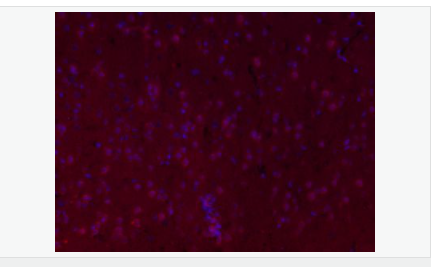

image.png